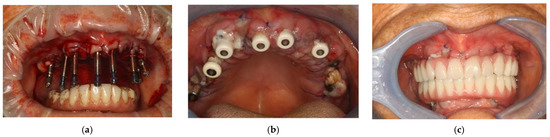

2. Materials, Methods and Results

Surgical Procedure